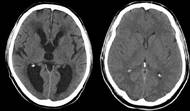

Mozek po mrtvici? Vědci objevili mechanismus přeprogramování, který pomáhá zotavení

Lidský mozek disponuje neuvěřitelnou schopností přežít. Mezinárodní tým vědců z projektu ENIGMA odhalil, že po těžké mrtvici dokáže nepoškozená polovina mozku doslova „omládnout“, aby kompenzovala ztracené funkce.